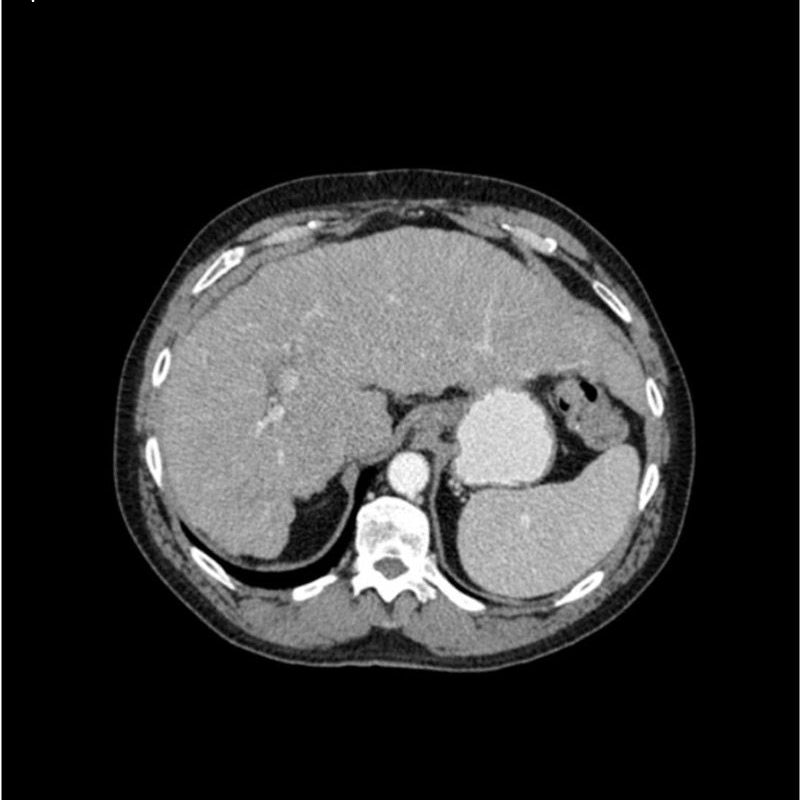

abdomen in portal venous phase. It covers the tenth thoracic vertebra to the third lumbar vertebra. The phantom represents an abdomen after cholecystectomy with small clips. The liver has typical signs of cirrhosis and there is an inferior vena cava filter implanted at the level of the third lumbar vertebra. Both kidneys have cystic lesions and there is a small kidney stone on the left side.

Realistic simulation of vasculature, bone and soft tissues, including the liver, pancreas, spleen, adrenals, kidneys, stomach, small intestine and colon.

- Liver cirrhosis

- cholecystectomy

- inferior vena cava filter

- kidney cysts

- kidney stone

- lymph nodes.